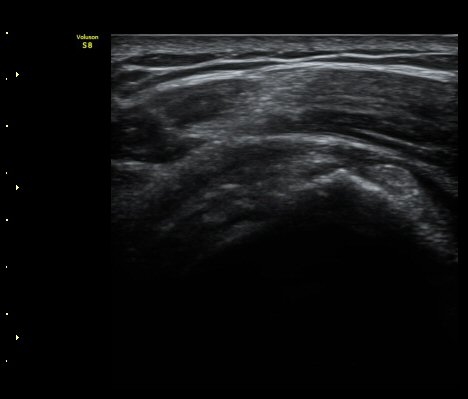

±Ø»ó°Ç Á¾´Ü¸é°Ë»ç¿¡¼­ Á¤¸Æ³¶³» ¼ö¾×Àú·ù¿Í ±Ø»ó°Ç³» ¼®È¸È­À½¿µÀÌ °üÂûµÈ´Ù(±×¸² 2, 3).